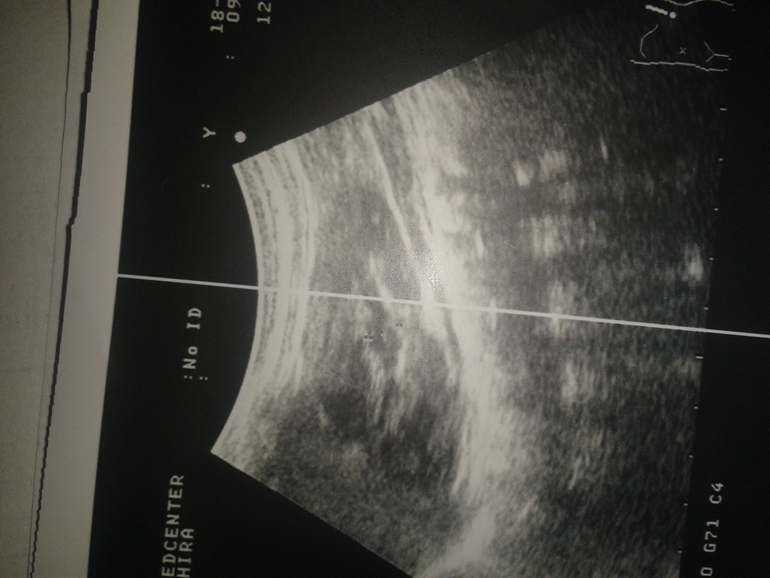

Вот декабрьское узи где лоханка 0, 7 см.

Здравствуйте, Максим Виктрович! С рождения пиелоэктазия у дочери 0, 7 см. Сейчас ей 7 месяцев. Сегодня на очередном УЗИ намеряли лоханку аж в 3 см!!! Причем узист уверял меня, что это пиелоэктазия и ничего страшного, никакой не гидронефроз.Что я начитаюсь и наслушаюсь "бабок на лавочках" и начинаю мерять лоханки. Но этоже 3 см!!!

Он первый кто измеряет нам лоханку вдоль, другие специалисты меряли как-то иначе